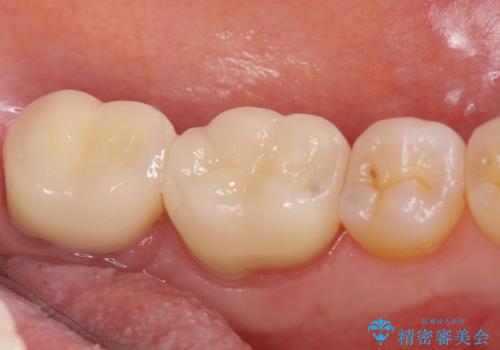

- 左下奥歯で咬むと違和感があるといらっしゃった方の症例です。

検査の結果左下7は失活(歯の神経が死んでいること)しておりX線上で根尖病変を認めたため、根管治療を行いました。

また左下6は遠心にあった歯茎より深い虫歯(縁下カリエス)の問題を解決するため、歯茎を下げる歯周外科手術を行いました。

歯周外科手術終了後、歯茎の回復を待ち左下6、7ともにオールセラミッククラウン(スタンダード)による補綴を行いました。